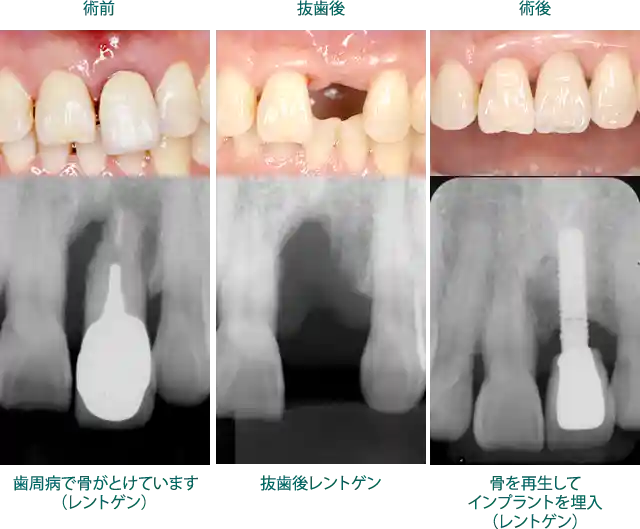

ケーススタディ2:歯周病で骨が溶けてしまった患者様

抜歯後、骨を再生しインプラントを埋入した症例

このケースは歯周病に罹患し、抜歯時期が遅れて骨の吸収が高度に進行しています。骨の造成量も多くなりますので、難易度が増します。

骨造成には造成量により別途費用(¥121,000【税込】~)がかかります。

① 費用:¥479,600【税込】~

②リスク:骨の造成が不可能な場合や造成量や骨の質等によりインプラントができない場合があります。また、チタンアレルギーのある方には使用できません。